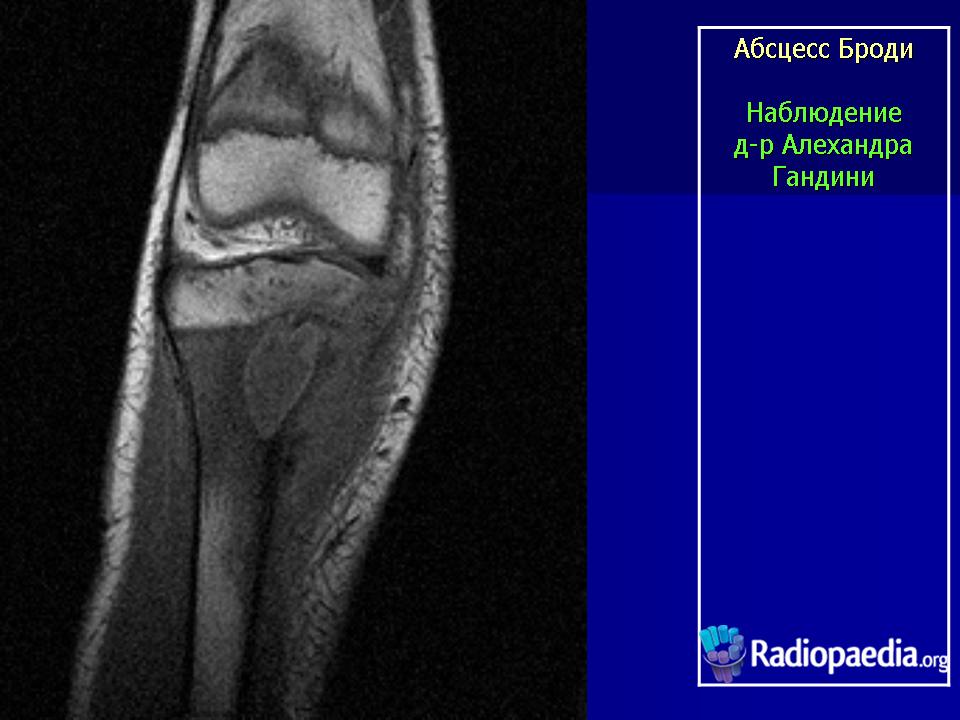

Абсцесс Броди (внутрикостный) - отграниченный некроз губчатого вещества кости, при котором происходит последующее ее расплавление и образование полости. Преимущественная локализация - проксимальный отдел болыпеберцовой кости. Возбудитель, как правило, стафилококк.

Как правило, в метафизе болыпеберцовой кости образуется полость диаметром 2-2,5 см. Полость заполнена гнойной, серозной или кровянистой жидкостью, иногда в ней находят тканевый детрит.

Абсцесс Броди (вялотекущий первично хронический внутрикостный абсцесс; МКБ–10: М86.8 Другой остеомиелит) заболевание, характеризующееся образованием в губчатом веществе эпифиза небольшой полости, заполненной гноем. Чаще у лиц молодого возраста, после окостенения эпифизарной пластинки роста. Локализуется в основном в верхнем или нижнем эпифизе большеберцовой кости, в метафизах бедренной и плечевой костей, реже в других длинных костях, иногда в костях позвоночника, стопы и др..

Рентгенологически обнаруживают полость с чёткими склерозированными контурами, при обострении периостальные наслоения, остеосклероз.

Особенностью гнойника Броди является локализация в губчатом костном веществе, причем практически почти никогда не поражаются мелкие или плоские кости, а исключительно большие трубчатые кости, а именно метафизарные концы. На первом месте по частоте заболевания стоят суставные концы костей, образующих коленный, голеностопный и локтевой суставы. Самым типичным и излюбленным местом локализации гнойника является большеберцовая кость, на долю которой выпадает 80% всех случаев, причем проксимальный метафиз поражается чаще, чем дистальный. Гнойник предпочтительно располагается поверхностно, под корковым слоем кости.

Абсцесс возникает в метафизарном губчатом веществе в детском или юношеском возрасте, до исчезновения эпифизарного хрящевого диска. Процесс с самого начала остается локализованным. Ограниченный участок губчатого вещества некротизируется и медленно рассасывается. Ранний и резко выраженный реактивный процесс вокруг гнойного очага ведет к образованию плотной пиогенной оболочки и остеосклерозу стенок гнойника. Поэтому дальнейший рост полости происходит крайне медленно — в течение годов и даже десятков лет, и вовсе прекращается, когда стенки достигают твердого, неподатливого компактного слоя. После обызвествления росткового хряща гнойник из метафиза несколько продвигается в эпифиз.

Форма полости — всегда правильная шаровидная или овальная с длинным диаметром, совпадающим с длинником кости. Величина различна, чаще всего полость имеет диаметр в 2—3 см. Изнутри полость выстлана плотной кожистой гноеродной пленкой (membrana pyogenica). Количество гноя различно. Редко он заполняет полость под давлением, иногда имеет характер застарелых полувысохших крошковатых масс. В некоторых случаях гной стерилен, в других же, через два и три десятилетия после начала заболевания, гной еще содержит вирулентные стафилококки.

Рис. 208. Хронический костный абсцесс Броди в верхнем метафизе большеберцовой кости.

Рис. 207. Хронический костный абсцесс Броди у 22-летнего больного. Болен 7 лет, периодически боли в коленном суставе и „симпатический” перемежающийся экссудативный гонит. Оперативное и гистологическое подтверждение диагноза.

Характерен для абсцесса Броди значительный остеосклероз губчатого вещества, окружающего полость, и лишь очень редко гнойник лежит среди нормальной спонгиозной ткани. На поверхности кости периостальные наслоения очень незначительны, так что если вообще имеется цилиндрическое или, скорее, веретенообразное утолщение метафиза на уровне гнойника, то только в самой умеренной степени. Как правило, секвестрации не бывает. До прорыва наружу или в полость соседнего сустава, несмотря на его близость, дело доходит лишь в редчайших случаях.

Рентгенологическое исследование имеет решающее диагностическое значение. Все детали патологоанатомической картины абсцесса Броди передаются в точности и на рентгеновских снимках (рис. 207 и 208). Изолированная, правильной округлой формы полость, без секвестра, с резко ограниченными гладкими внутренними контурами, расположенная среди склерозированного губчатого вещества, на типичном месте — в метафизарном конце большой трубчатой кости, слегка утолщенной благодаря периостальным наслоениям, — эта рентгенологическая картина при поддержке клинических симптомов разрешает диагностическую задачу. При этом следует учесть, что между, так сказать, классическим типичным абсцессом Броди и другими формами хронического остеомиелита бывают и переходные формы — и по местоположению, размерам, форме, характеру реактивных изменений в окружности, секвестрации и т. д. Это ведь в природе вещей: классификация показывает всегда несколько условно типичное, жизнь преподносит многообразие, не укладывающееся в строгую жесткую схему. Никоим образом не следует злоупотреблять диагнозом абсцесса Броди и ставить его расширительно, чуть ли не во всех случаях более или менее ясно выраженной полости при обычном хроническом остеомиелите: абсцесс Броди — это совершенно определенное клинико-рентгено-анатомическое понятие, это четкая нозологическая единица, и диагноз оправдан лишь в тех случаях, когда рентгенологическая картина удовлетворяет всем вышеперечисленным критериям.